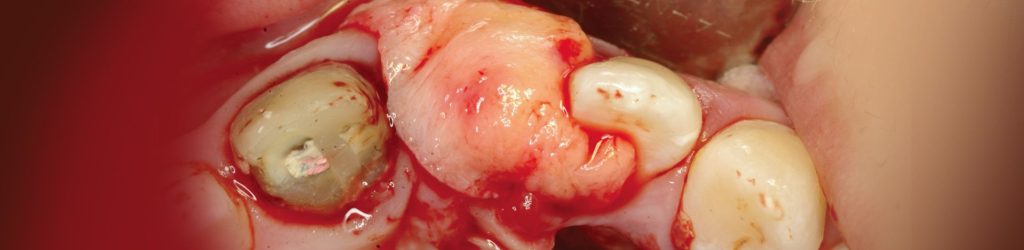

בסמוך למרפאתנו הקמנו חדר הרצאות חדשני וייחודי. ייעודו של האגף החדש הינו להגשים חלום יקר לליבנו, לממש ולקיים מרכז להכשרה קלינית לרופאים ובהדרכה אישית: A PRIVATE ACADEMY. במרכז יתקיימו הרצאות, קורסים עיוניים ומעשיים בהם תהיה צפייה בניתוחים בשידור חי, מחדר הניתוח בזכות מיטב הטכנולוגיה החדשנית. במתחם החדש, אנו נארגן מגוון רב של פעילויות, ומאמינים כי ביכולתנו לתרום מניסיוננו לטובת ציבור רופאי השיניים הכלליים. הקורסים מיועדים לכלל ציבור רופאי השיניים המעוניינים להעשיר את בסיס הידע ואת יכולתם הקלינית בתחומים שונים (פריודונטיה, אימפלנטולוגיה ואסתטיקה), דבר שישרת אותם במרפאתם. המרצים יהיו רופאי המרפאה יחד עם רופאים בכירים ומומחים נוספים אשר יצטרפו לצוות.